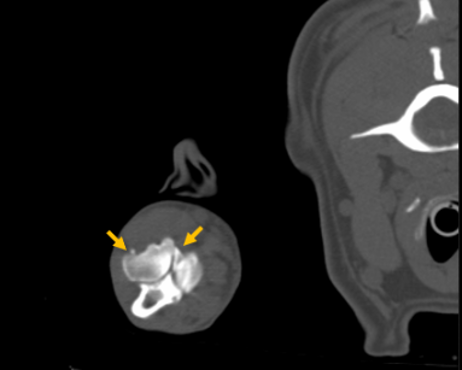

영상 검사 – CT로 확인된 원인

초기 엑스레이 검사에서는 뚜렷한 이상이 확인되지 않았습니다. 하지만 FMCP는 작은 뼛조각이 원인이 되는 질환이기 때문에, 보다 정밀한 검사가 필요하다고 판단되어 CT 촬영을 진행하였고, 그 결과 척골 내측 구상돌기의 분리된 뼛조각이 명확하게 확인되었습니다.

대형견 강아지 FMCP CT 촬영 / 출처: 에스동물메디컬센터

최종적으로 대형견 강아지는 다음과 같은 최종 진단을 받게 되었습니다.

📌 대형견 강아지 앞다리 절뚝거림 최종 진단

✔️ 내측 구상돌기 분리증(FMCP)

✔️ 이차적인 퇴행성 관절염(Degenerative Joint Disease)

특히 이미 연골 손상이 일부 진행된 상태로 판단되어, 빠른 치료가 필요한 상황이었습니다.